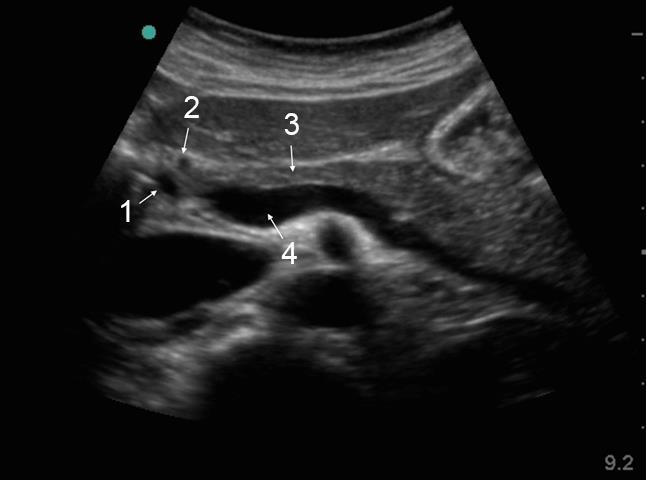

胆嚢注意 – 総胆管(CBD)の画像

総胆管(CBD)

胃十二指腸動脈

膵臓

脾静脈